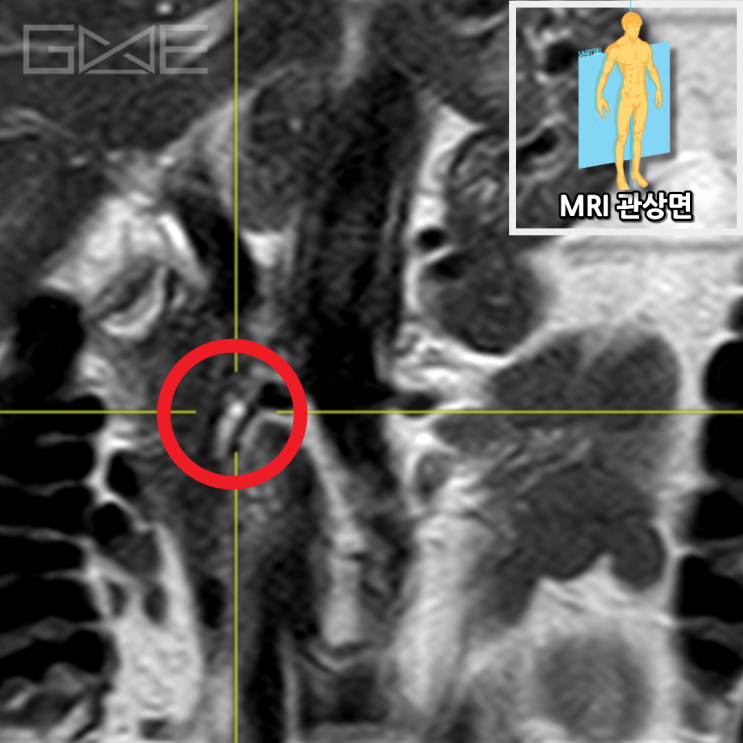

자기공명담췌관조영술상에서 췌장구상돌기 쪽으로 약 1.1cm 가량의 물혹이 보이고 있으며, 이는 췌장담도와 연결성이 보이고 있습니다. 이에 췌관내유두점액낭종으로 생각이 되며, 이에 대해서 추적 관찰을 하기로 하였습니다.

• 췌장MRI 관상면: 췌장구상돌기 부위 물혹(빨간 동그라미) 췌장MRI 관상면: 췌장구상돌기 부위 물혹(빨간 동그라미)